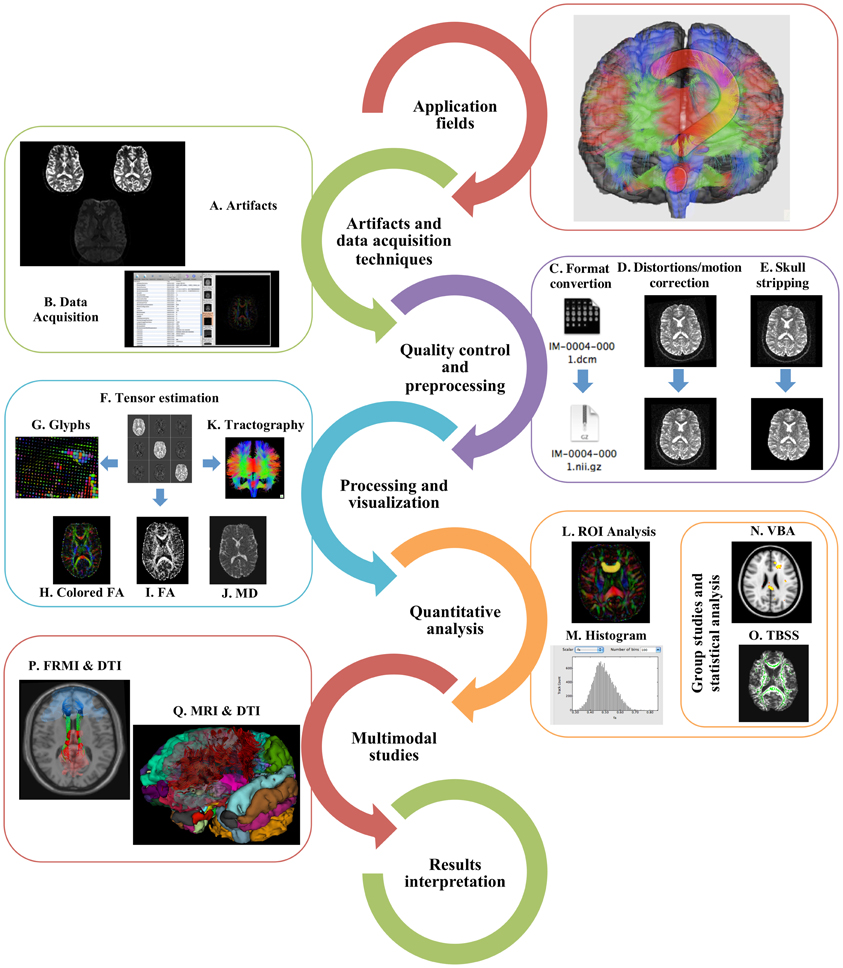

Frontiers | A hitchhiker's guide to diffusion tensor imaging

Fig 1. | Diffusion Tensor Imaging as Potential Biomarker of White

A) Diffusion tensor imaging (DTI)-based whole-brain tractogram in